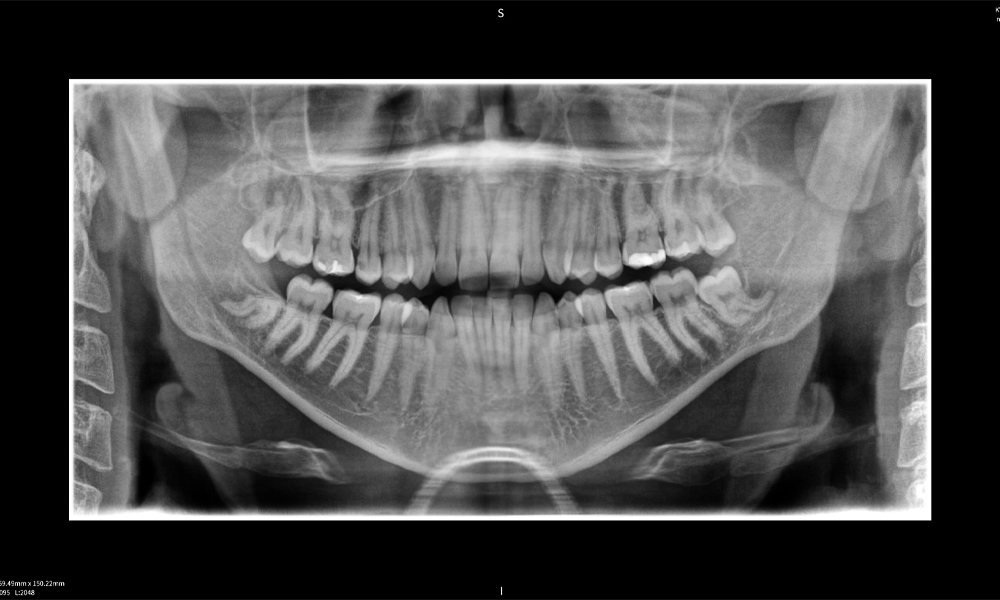

A continuación encontrarás un caso del Dr. med. dent. Oliver A. Centrella, en el cual las imágenes CBCT obtenidas con Seethrough Max proporcionaron información crucial sobre la anatomía compleja y la relación crítica entre las muelas del juicio y el nervio alveolar inferior. En este caso, existe una indicación para la extracción quirúrgica de las muelas del juicio.

Figura a: Resultados de imagen de Seethrough Max, sobre un fondo negro.

Figura a

Figura e: La radiografía panorámica sirve como herramienta de evaluación inicial, mostrando la posición general de los dientes, así como posibles cambios patológicos. Es notable que en el lado derecho (diente 48) se observa la situación posterior a una amputación de corona realizada por un profesional externo. Las dos raíces fuertemente curvadas permanecen en estrecha proximidad topográfica al nervio alveolar inferior dentro del hueso. Esto sugiere una decisión deliberada de evitar el mayor riesgo de lesión nerviosa durante una extracción completa y representa un hallazgo clínicamente relevante. En resumen, las tomografías CBCT con Seethrough Max proporcionan información crucial sobre la anatomía compleja y la relación crítica entre las muelas del juicio y el nervio alveolar inferior. Esta imagenología diagnóstica detallada preoperatoria es esencial para realizar procedimientos quirúrgicos seguros y exitosos en la región mandibular.